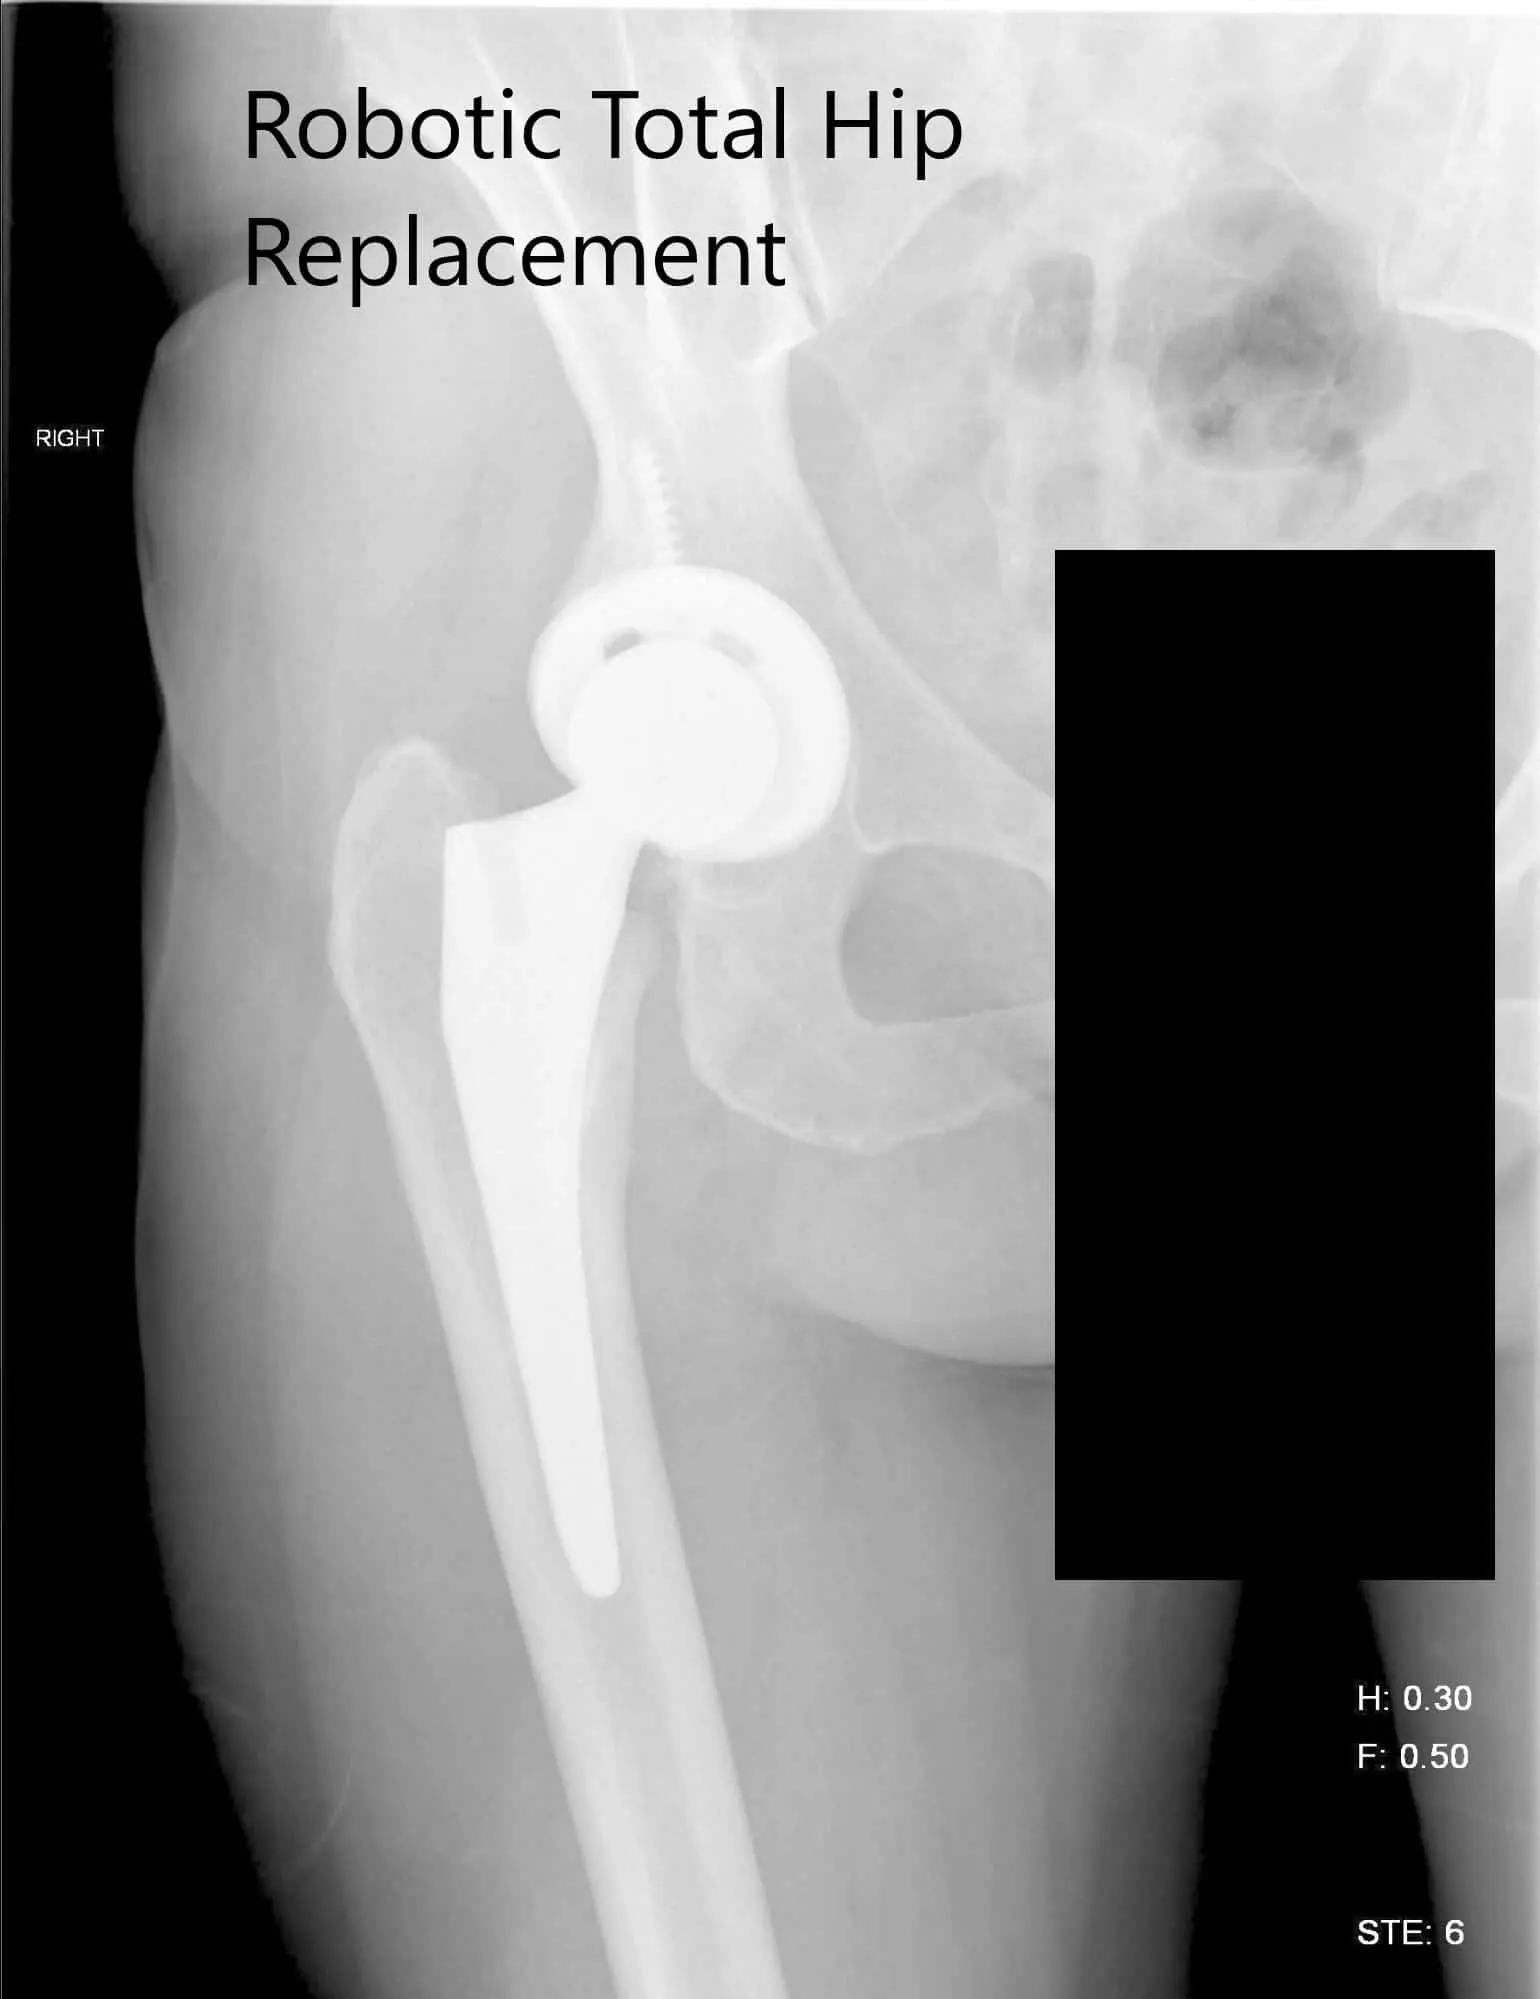

OPERATION: Robotic right total hip replacement.

IMPLANTS USED: Tritanium cluster shell 52-mm with 6.5-mm x 30-mm screw with a Trident shell. Zero degrees poly with a 127-degree stem with a ceramic head, outer diameter 32-mm minus 4.

Postoperative X-ray of the right hip showing AP and lateral view.